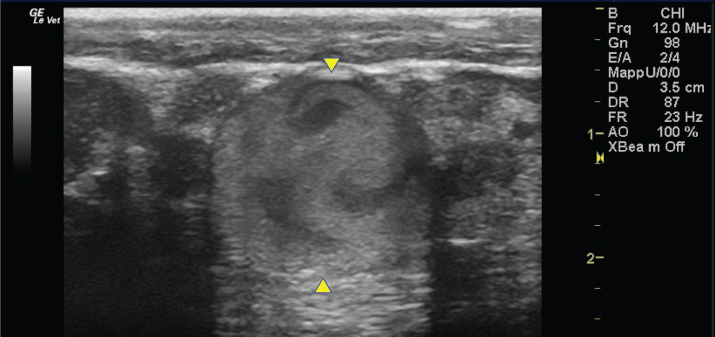

The left jugular vein appeared as an anechoic tubular structure which collapsed under the probe pressure, the color Doppler examination revealed normal blood flow within the vessel (Fig. 3). Bi-dimensional ultrasonography of the right jugular vein showed a heterogeneous, non-cavitating, hypoechoic structure occluding a narrowed right jugular vein for about 30 cm of length localized in the proximal and mid-portion of the neck compatible with a thrombus (Fig. 4). The color Doppler examination showed blood flow through the lateral portions of the thrombus in the cranial and mid-portions of the right jugular vein (Fig. 5). Cranially to the thrombus, a marked distension of the maxillary and linguofacial veins was evident, with a turbulent and echogenic flow; the latter was compatible with blood stasis near the thrombus (Fig. 6). Caudally to the thrombus, the right jugular vein presented reduced diameter, thickened walls, and normal blood flow (Fig. 7). The cranial part of the thrombus originated from a heterogeneous scare tissue, localized at the level of the right mandibular angle (Fig. 8). After injection of the first saline contrast bolus in a right facial vein, no microbubbles appeared in the right jugular vein, caudally to the thrombus, proving the presence of a complete right jugular vein occlusion. On the contrary, after injection of the second bolus, microbubbles were visualized in the left jugular vein as small, intense, echo signals within the vein lumen, demonstrating the presence of collateral circulation that drained the blood from the right facial veins to the left jugular vein (Fig. 9). Venography results confirmed the complete occlusion of the right jugular vein and the presence of submandibular venous collaterals that connected the right facial veins with the left jugular vein (Figs. 10 and 11). Based on the previous results, the diagnosis of JVT with complete occlusion of the vessel lumen was confirmed. The horse’s owner refused any proposed medical or surgical therapy.

Fig. 9. Bi-dimensional ultrasonographic image of the left jugular vein in longitudinal section (arrows). Microbubbles appeared as small, intense, echo signals that passed in the vein lumen following agitated saline injection.